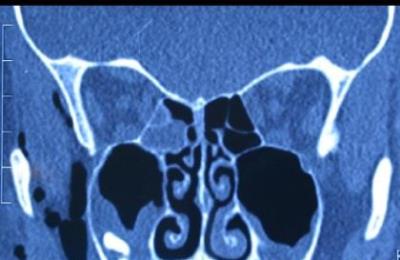

Диагностика болезни

Выявить катаральный гайморит на рентген-снимке, как правило, невозможно, поскольку потемнение области гайморовых пазух наблюдается только при появлении гнойного отделяемого, что не характерно для данной формы недуга.

Диагностика катарального гайморита обычно включает осмотр пациента отоларингологом, который может использовать риноскопию для оценки состояния носовых проходов. В некоторых случаях могут быть назначены дополнительные исследования, такие как рентгенография или компьютерная томография, для более детального изучения состояния гайморовых пазух.